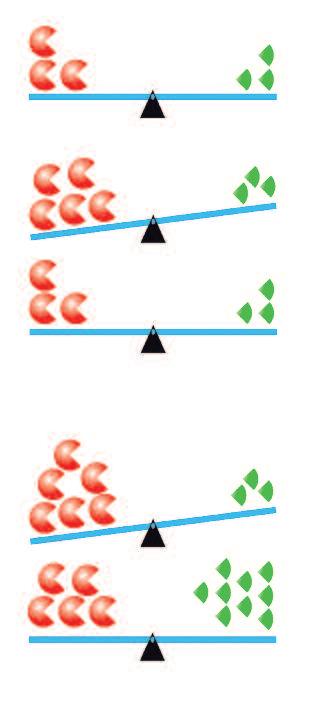

Un secondo fatto importante mostrato nella figura a fronte è l'equilibrio tra il meccanismo di demolizione del collagene (rosso) e i suoi meccanismi di blocco (blu e verde) durante periodi di salute e malattia. Ad esempio, quando si combattono le infezioni, i globuli bianchi migrano attraverso il corpo creando uno squilibrio momentaneo a favore della degradazione del collagene, abbastanza a lungo da consentire il passaggio dei leucociti verso il sito dell’infezione. Una volta migrati, il corpo sano ristabilisce l'equilibrio in pochi istanti.

Nel cancro questo equilibrio è definitivamente spostato verso la degradazione del collagene e i ‘blocchi’ interni non sono sufficienti per fermare la distruzione del tessuto connettivo. In questa situazione, un elevato apporto nutrizionale di lisina e di altri fattori alimentari ‘bloccanti’ è il modo più efficace per ripristinare l'equilibrio del tessuto connettivo e di eseguire la riparazione.

Enzimi collagenasi

Difesa naturale del sistema immunitario

Difesa naturale dei micronutrienti (lisina)

Salute è data

produzione regolata o temporaneo squilibrio subito riassorbito

Malattia è data squilibrio cronico

prevenzione e correzione

Integrazione di quantità maggiori di lisina e di altri micronutrienti inibitori tramite la nutrizione